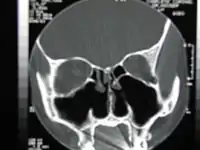

![]() الاشعة المقطعية للأنف بعد استئصال المحارات الثنائية الكلية | |